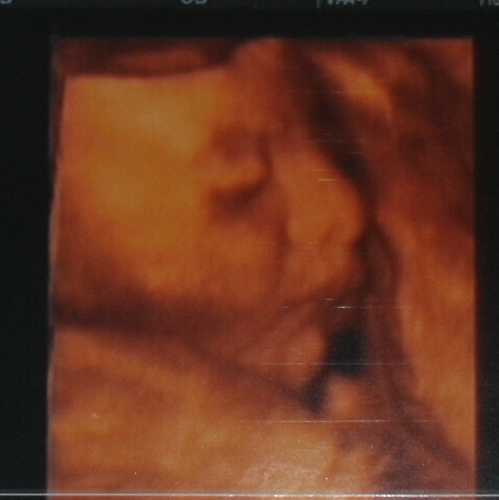

Nagyon gyönyörű a kis pofija